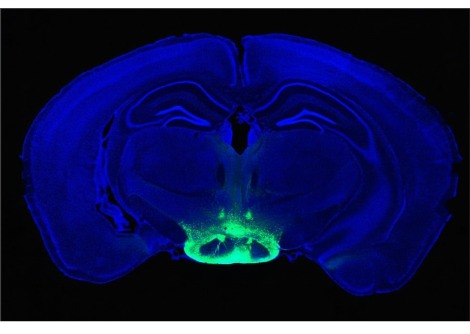

أعلن الباحثون في دراسة أجريت في نيسان من عام 2017 في مجلّة "علم وظائف الأعضاء" أنّ الخلايا الموجودة في عيون الفئران تصدر جزيء يسمّى "فاسوبريسين" Vasopressin والذي يتوجّه للدماغ مساعداً في تنظيم الساعة البيولوجية.